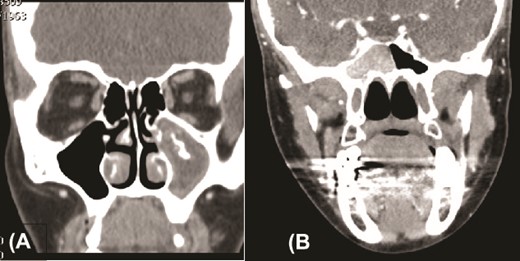

We present a case of a 52-year-old female, not known to have any chronic disease, who presented to our institution’s otorhinolaryngology clinic with a complaint of headache, facial pain, and PND for 6 months. Endonasal endoscopic examination was unremarkable. A paranasal sinus CT was requested to aid the diagnosis, which showed two simultaneous opacities occupying the left maxillary and right sphenoid sinuses, respectively (Fig. 1A and B). The opacified lesions were associated with calcifications, metallic shadowing, and bony thickening of the sinus wall. According to the history and radiological imaging findings, a diagnosis of a fungal ball occupying both the maxillary and sphenoid sinuses was achieved, and a functional endoscopic sinus surgery (FESS) with left wide maxillary antrostomy removal of the thick fungal debris occupying the left maxillary sinus (Fig. 2) was decided to be performed. In addition, a wide endoscopic sphenoidotomy was performed, and the sphenoid sinus was full of fungal debris (Fig. 3), which was cleaned thoroughly. The patient had an uneventful post-operative course.

Paranasal sinuses CT scan, coronal view, showing left maxillary sinus fungal ball (A) and a right sphenoid fungal ball (B).